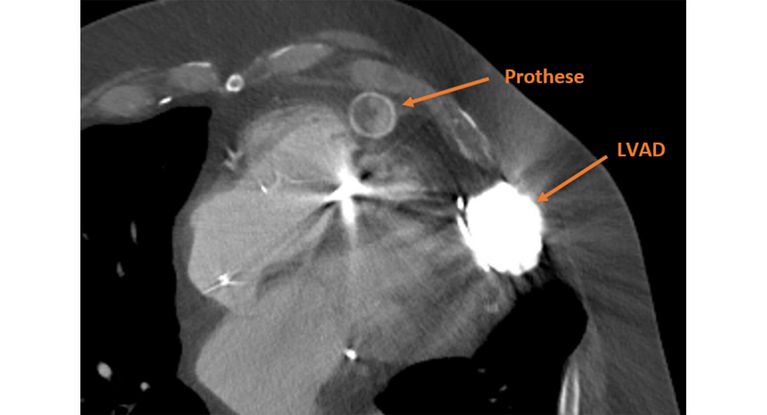

CT: LVAD an der linken Herzkammer sowie die Prothese zur Aorta mit Verengung (dunkler Bereich innerhalb der Prothese).